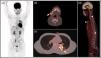

Ante la sospecha de una tuberculosis diseminada, se decidió completar estudio de extensión con una TC de tórax, que mostró únicamente consolidaciones parcheadas bilaterales, lo que indicaba la existencia de tuberculosis pulmonar reactivada, y una [18F]-FDG PET/TC, que evidenció múltiples lesiones hipermetabólicas en parénquima pulmonar de predominio izquierdo, con afectación ganglionar supradiafragmática, lesiones hepáticas y óseas de alto grado metabólico, que parecían corresponderse con el mismo proceso infeccioso (fig. 3).

A) [18F]-FDG PET/TC mostró múltiples lesiones hipermetabólicas en parénquima pulmonar, de predominio izquierdo, con afectación ganglionar supradiafragmática, hepática y numerosas lesiones óseas de alto grado metabólico (MIP). B) Adenopatía hipermetabólica submandibular derecha (imagen axial). C) Lesiones pulmonares izquierdas de alto grado metabólico (imagen axial). D) Afectación ósea vertebral y esternal (imagen sagital).